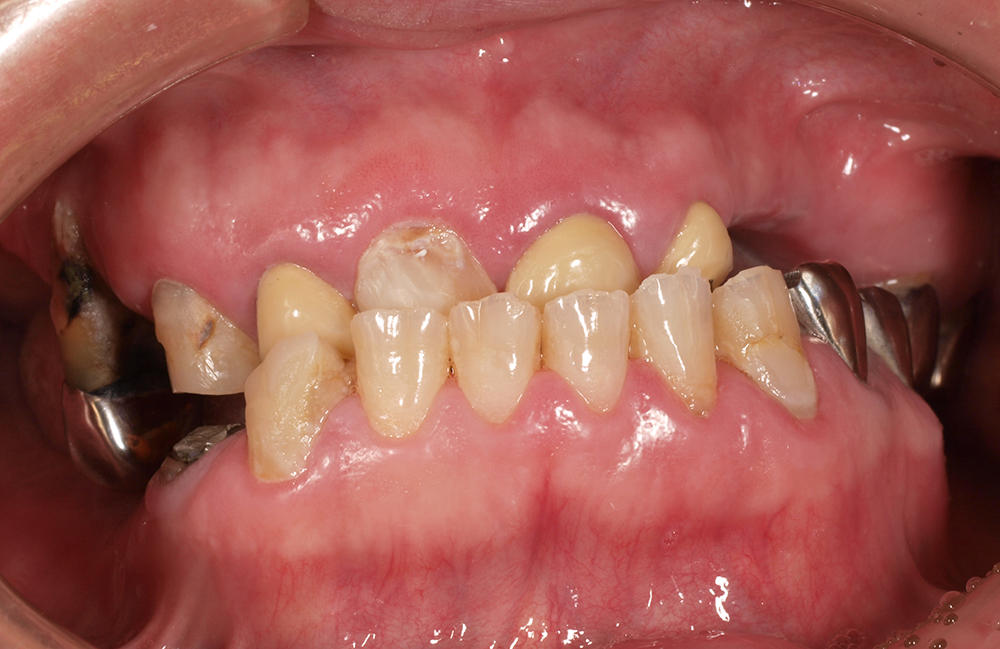

53歳 男性

- 主訴

- 全然噛めない。上の歯が取れてきた

- 処置内容

- 上顎:8本 下顎:2本

- 治療費用

- 上顎:約320万円(税込)、下顎:約160万円(税込)

- 治療期間

-

上顎:1年(仮歯まで8か月)

下顎:8か月(仮歯まで5か月)

- リスク

- 上部構造物、仮歯の破折、術後の腫れ(3日)、人工歯根脱落リスクがあります